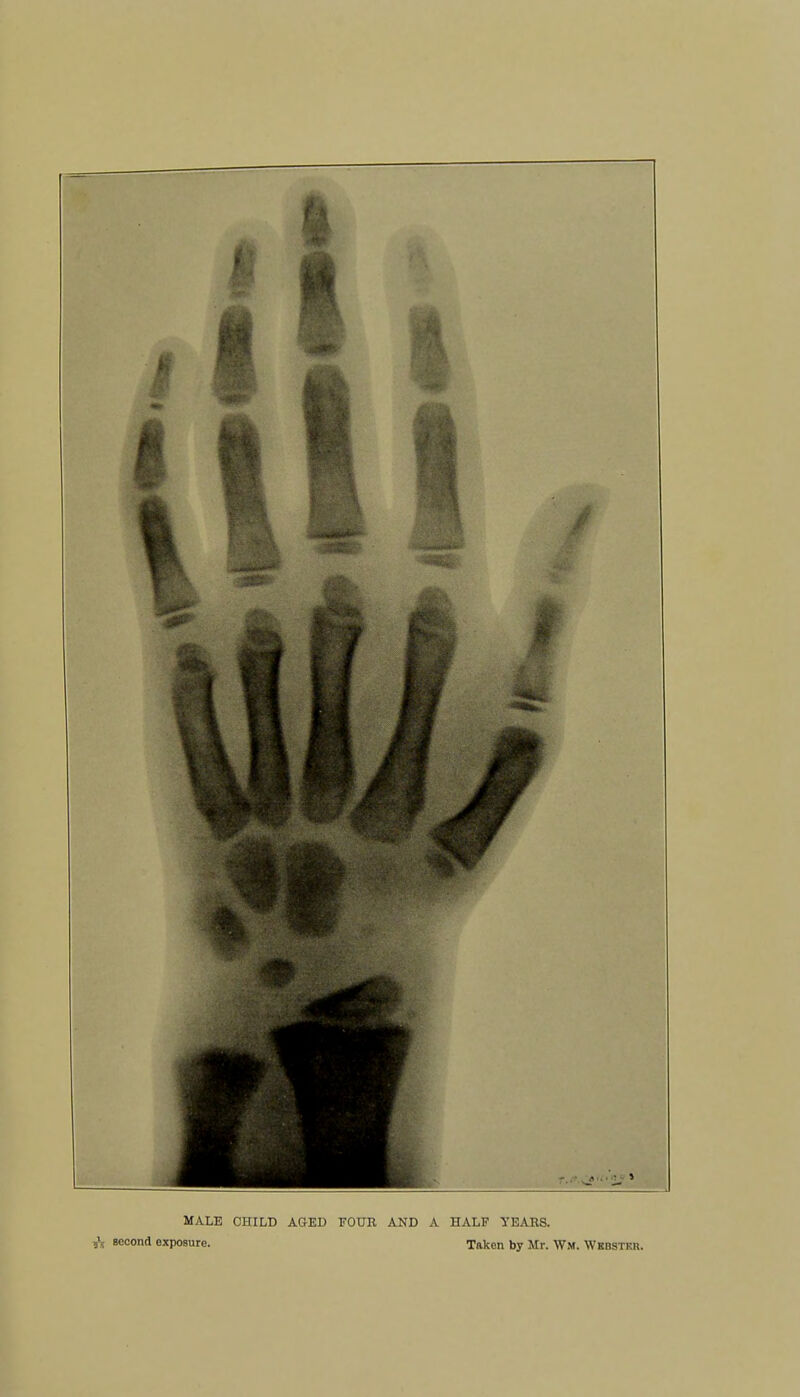

Skiagraphic atlas showing the development of the bones of the wrist and hand : for the use of students and others / by John Poland.

- Poland, John, 1855-1937

- 1898